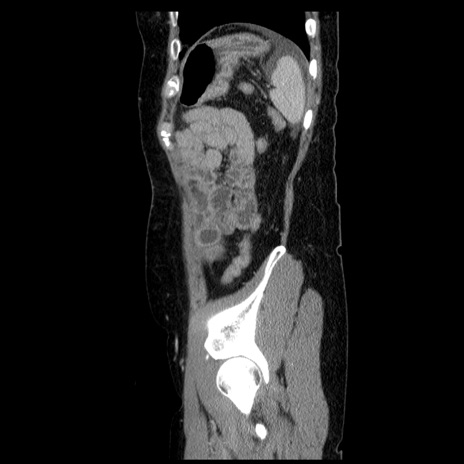

症例6(矢状断像)

【症例】50歳代女性

【主訴】下腹部痛

【現病歴】本日朝より下痢2回あり。 昼食を食べた後、嘔吐3回、下腹部痛認め、症状軽快せず、当院救急搬送。

最終食事:本日昼(生ものなし)。 昨日の夜、刺身を食ぺたとのこと。周囲に同様の症状の者なし。普段、排便は毎日あるとのこと。

【既往歴】卵巣癌術後(8年前に当院で卵巣摘出)

【身体所見】 意識清明、腹部:平坦、腸蠕動音→、やや硬、下腹部自発痛・圧痛あり、反跳痛あり、筋性防御なし。

【データ】WBC 16000、CRP 0.01